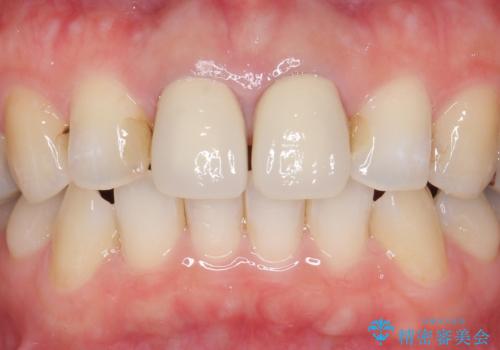

- 上顎の前から2番目の歯の古い樹脂をセラミックにしたいといらっしゃった方の症例です。

古い樹脂を除去後、オールセラミッククラウンによる補綴を行いました。